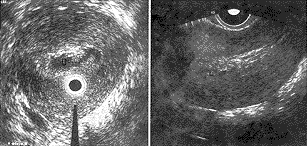

1、正常子宫 宫底部切面呈圆形,浆膜呈反射稍强、平滑、连续的细线。肌层为等回声,光点细小均匀,中央有整齐的圆形强光环系探头反射。宫角处及宫体两侧浆膜线不连续或缺失,使该处声像呈“鸟嘴”样或“慧星尾”状,肌层内近探头处可见内膜回声(厚度5.7±2.8mm),呈整齐的带状低回声,与肌层分界清晰(图1),宫颈部无浆膜线回声,肌层反射增强,有时可见清晰的“纳氏囊肿”暗区。

1.浆膜线;2.子宫肌层;3.正常的子宫内膜;

4.右侧宫角;5.左侧宫角

图1 正常子宫体切面